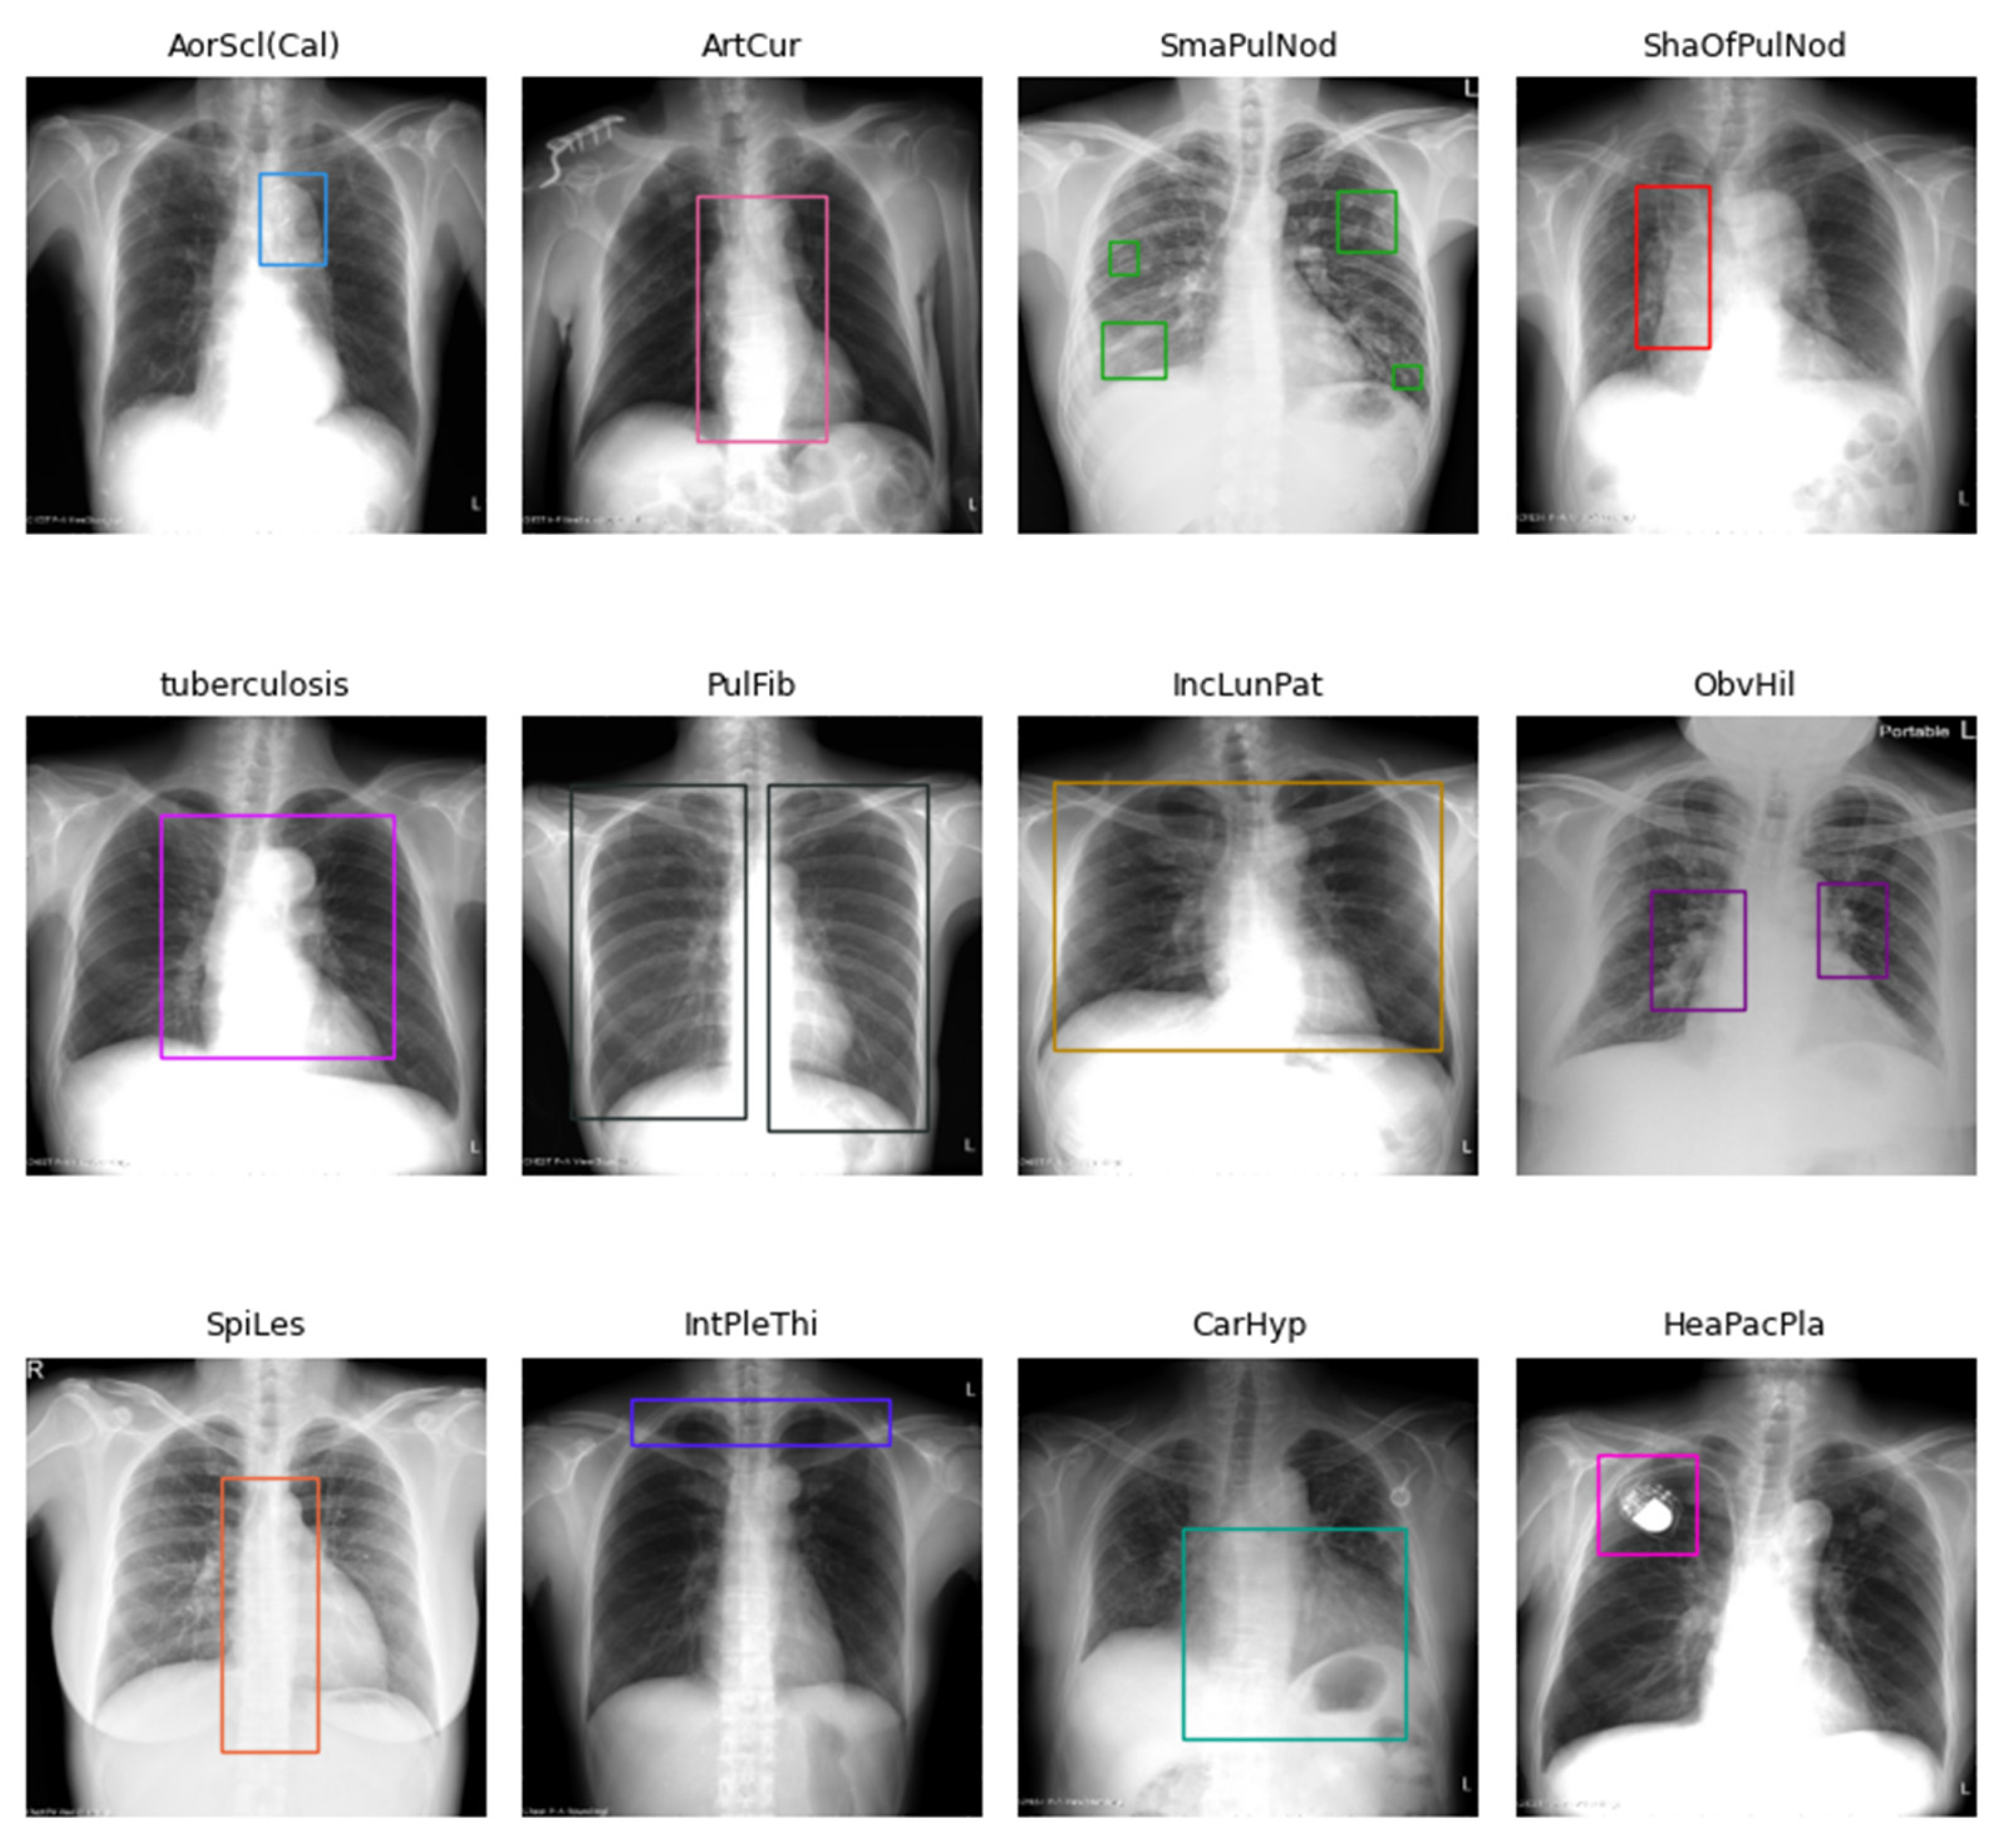

| Categories | Count | New Categories | Abbr. | Count |

| Normal | 1212 | Normal | Normal | 1212 |

| Aortic arch atherosclerotic plaque | 28 | Aortic sclerosis (calcification) | AorScl(Cal) | 83 |

| Aortic arch calcification | 16 | |||

| Aortic atherosclerosis | 25 | |||

| Aortic wall calcification | 20 | |||

| Aortic curvature | 65 | Arterial curvature | ArtCur | 93 |

| Thoracic vertebral artery curvature | 28 | |||

| Small pulmonary nodules | 15 | Small pulmonary nodules | SmaPulNod | 15 |

| Shadows of pulmonary nodules | 8 | Shadows of pulmonary nodules | ShaOfPulNod | 8 |

| Tuberculosis | 6 | Tuberculosis | tuberculosis | 6 |

| Pulmonary fibrosis | 30 | Pulmonary fibrosis | PulFib | 30 |

| Increased lung streak | 89 | Increased lung patterns | IncLunPat | 225 |

| Lung field infiltration | 138 | |||

| Obvious hilar | 55 | Obvious hilar | ObvHil | 55 |

| Degenerative joint disease of the thoracic spine | 75 | Spinal lesions | SpiLes | 170 |

| Scoliosis | 100 | |||

| Intercostal pleural thickening | 52 | Intercostal pleural thickening | IntPleThi | 52 |

| Cardiac hypertrophy | 41 | Cardiac hypertrophy | CarHyp | 41 |

| Heart pacemaker placement | 9 | Heart pacemaker placement | HeaPacPla | 9 |